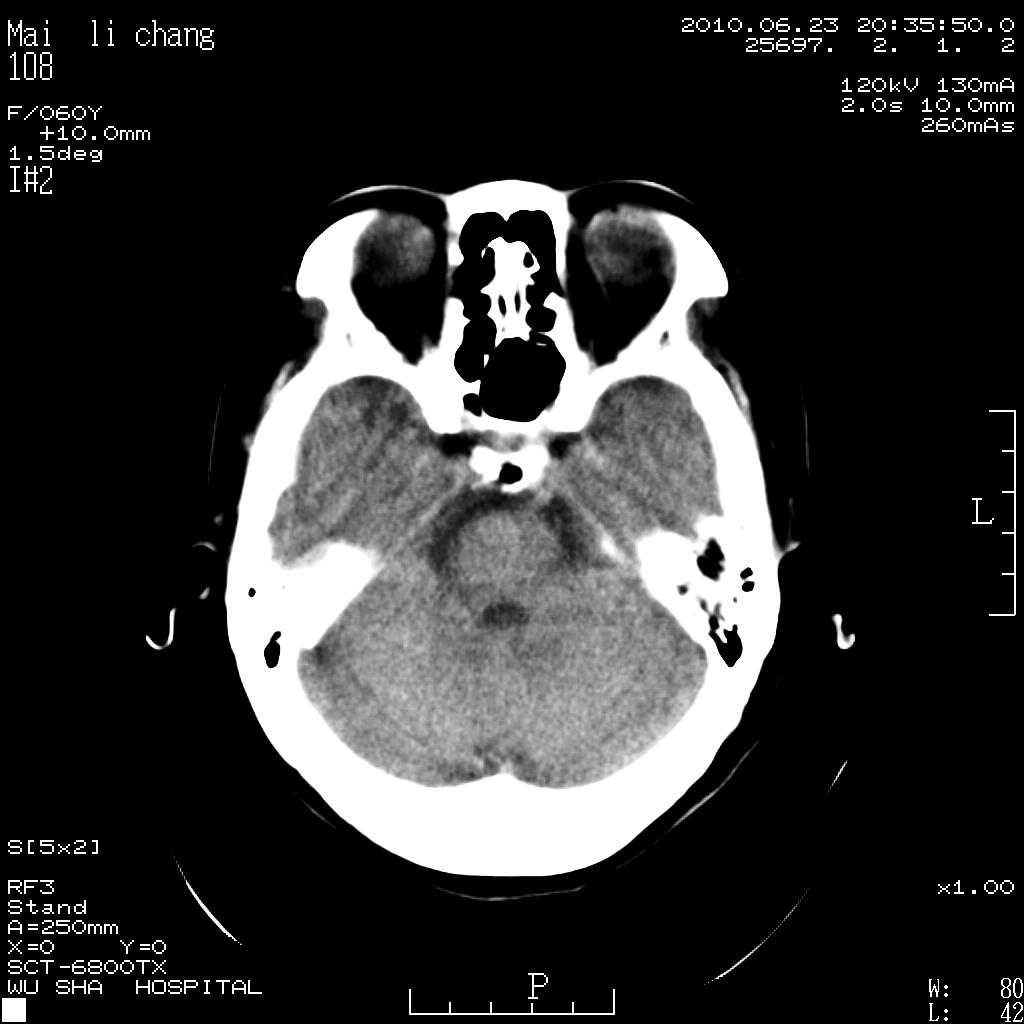

女性,60岁,右手无力一天

脑梗塞?并皮层下动脉硬化性脑病?还需要考虑什么?请大家指导,先谢了。

考虑左侧基底节区脑梗塞。

从提供的临床资料及影像检查不考虑皮层下动脉硬化性脑病。

左侧基底节区及放射冠区多发脑梗塞。

左侧基底节区及侧脑室旁多发脑梗塞